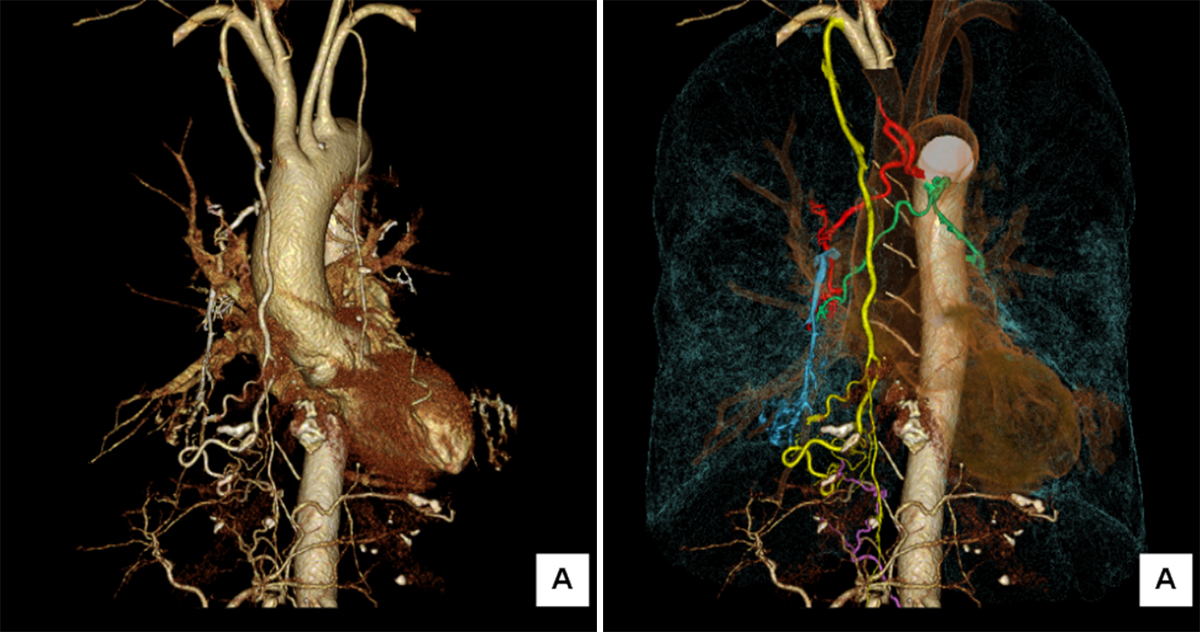

シャトルCTでは右気管支動脈、左気管支動脈から分岐する右気管支動脈の拡張蛇行、右内胸動脈の拡張と分枝の拡張蛇行、下横隔動脈の拡張蛇行を認めた (図2) 。また大動脈相の後期で右肺動脈への造影剤の逆流を認め、いわゆるBA-PAシャントの存在が疑われた (図3) 。以上の結果から喀血に対して気管支動脈等の塞栓術が適応と判断しカテーテル治療を行った。

図2 6相目の3D再構成

右は必要な血管を色分けして表示している

黄:右内胸動脈、赤:右気管支動脈、緑:左気管支動脈から分岐する右気管支動脈、紫:右下横隔動脈、青:肺動脈 (右A5) への造影剤の逆流